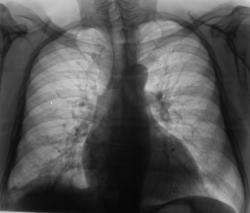

Пациент был направлен в рентгеновский кабинет терапевтом с диагнозом "Правостороняя пневмония". Было произведено стандартное исследование.

Было назначено противовоспалительное лечение. Через 1 неделю проведен "рентген-контроль".

Еще через неделю, также произведен "рентген-контроль".

Сегодня произвели "очередной контроль". Произвели рентгенографию в прямой и правой боковой проекциях. Решили также произвести томографию в правой боковой проекции.

правостороннего плеврального выпота в проекции средней доли.

Согласен с коллегой, но по-моему, кроме это выпот есть и заднем синусе. Картина в серия снимков №7-9, с небольшой положительной динамикой в сравнении данными в серии №4-6.

Кажущееся затемнение в области средней доли симулирует суперпозиция приподнятого правого купола диафрагмы и тени сердца. В заднем синусе справа - небольшой выпот, а со стороны диафрагмы, кроме элевации и выпрямления, присутствует картина диафрагматита в задних отделах. Вероятно необходимо ультразвуковое исследование органов брюшной полости и забрюшинного пространства для поиска первопричины данного состояния там. Динамика процесса за время наблюдения - явно положительная.

Катенёву В.Л.: На боковых томограммах, впечатление о инфильтрации с распадом в S10; томограммы, вероятно выполнены в положении лёжа, следовательо следует ожидать, что выпот растекся по грудной стенке и  не виден. С учётом характера распада, не исключаеиться туберкулёзный процесс.